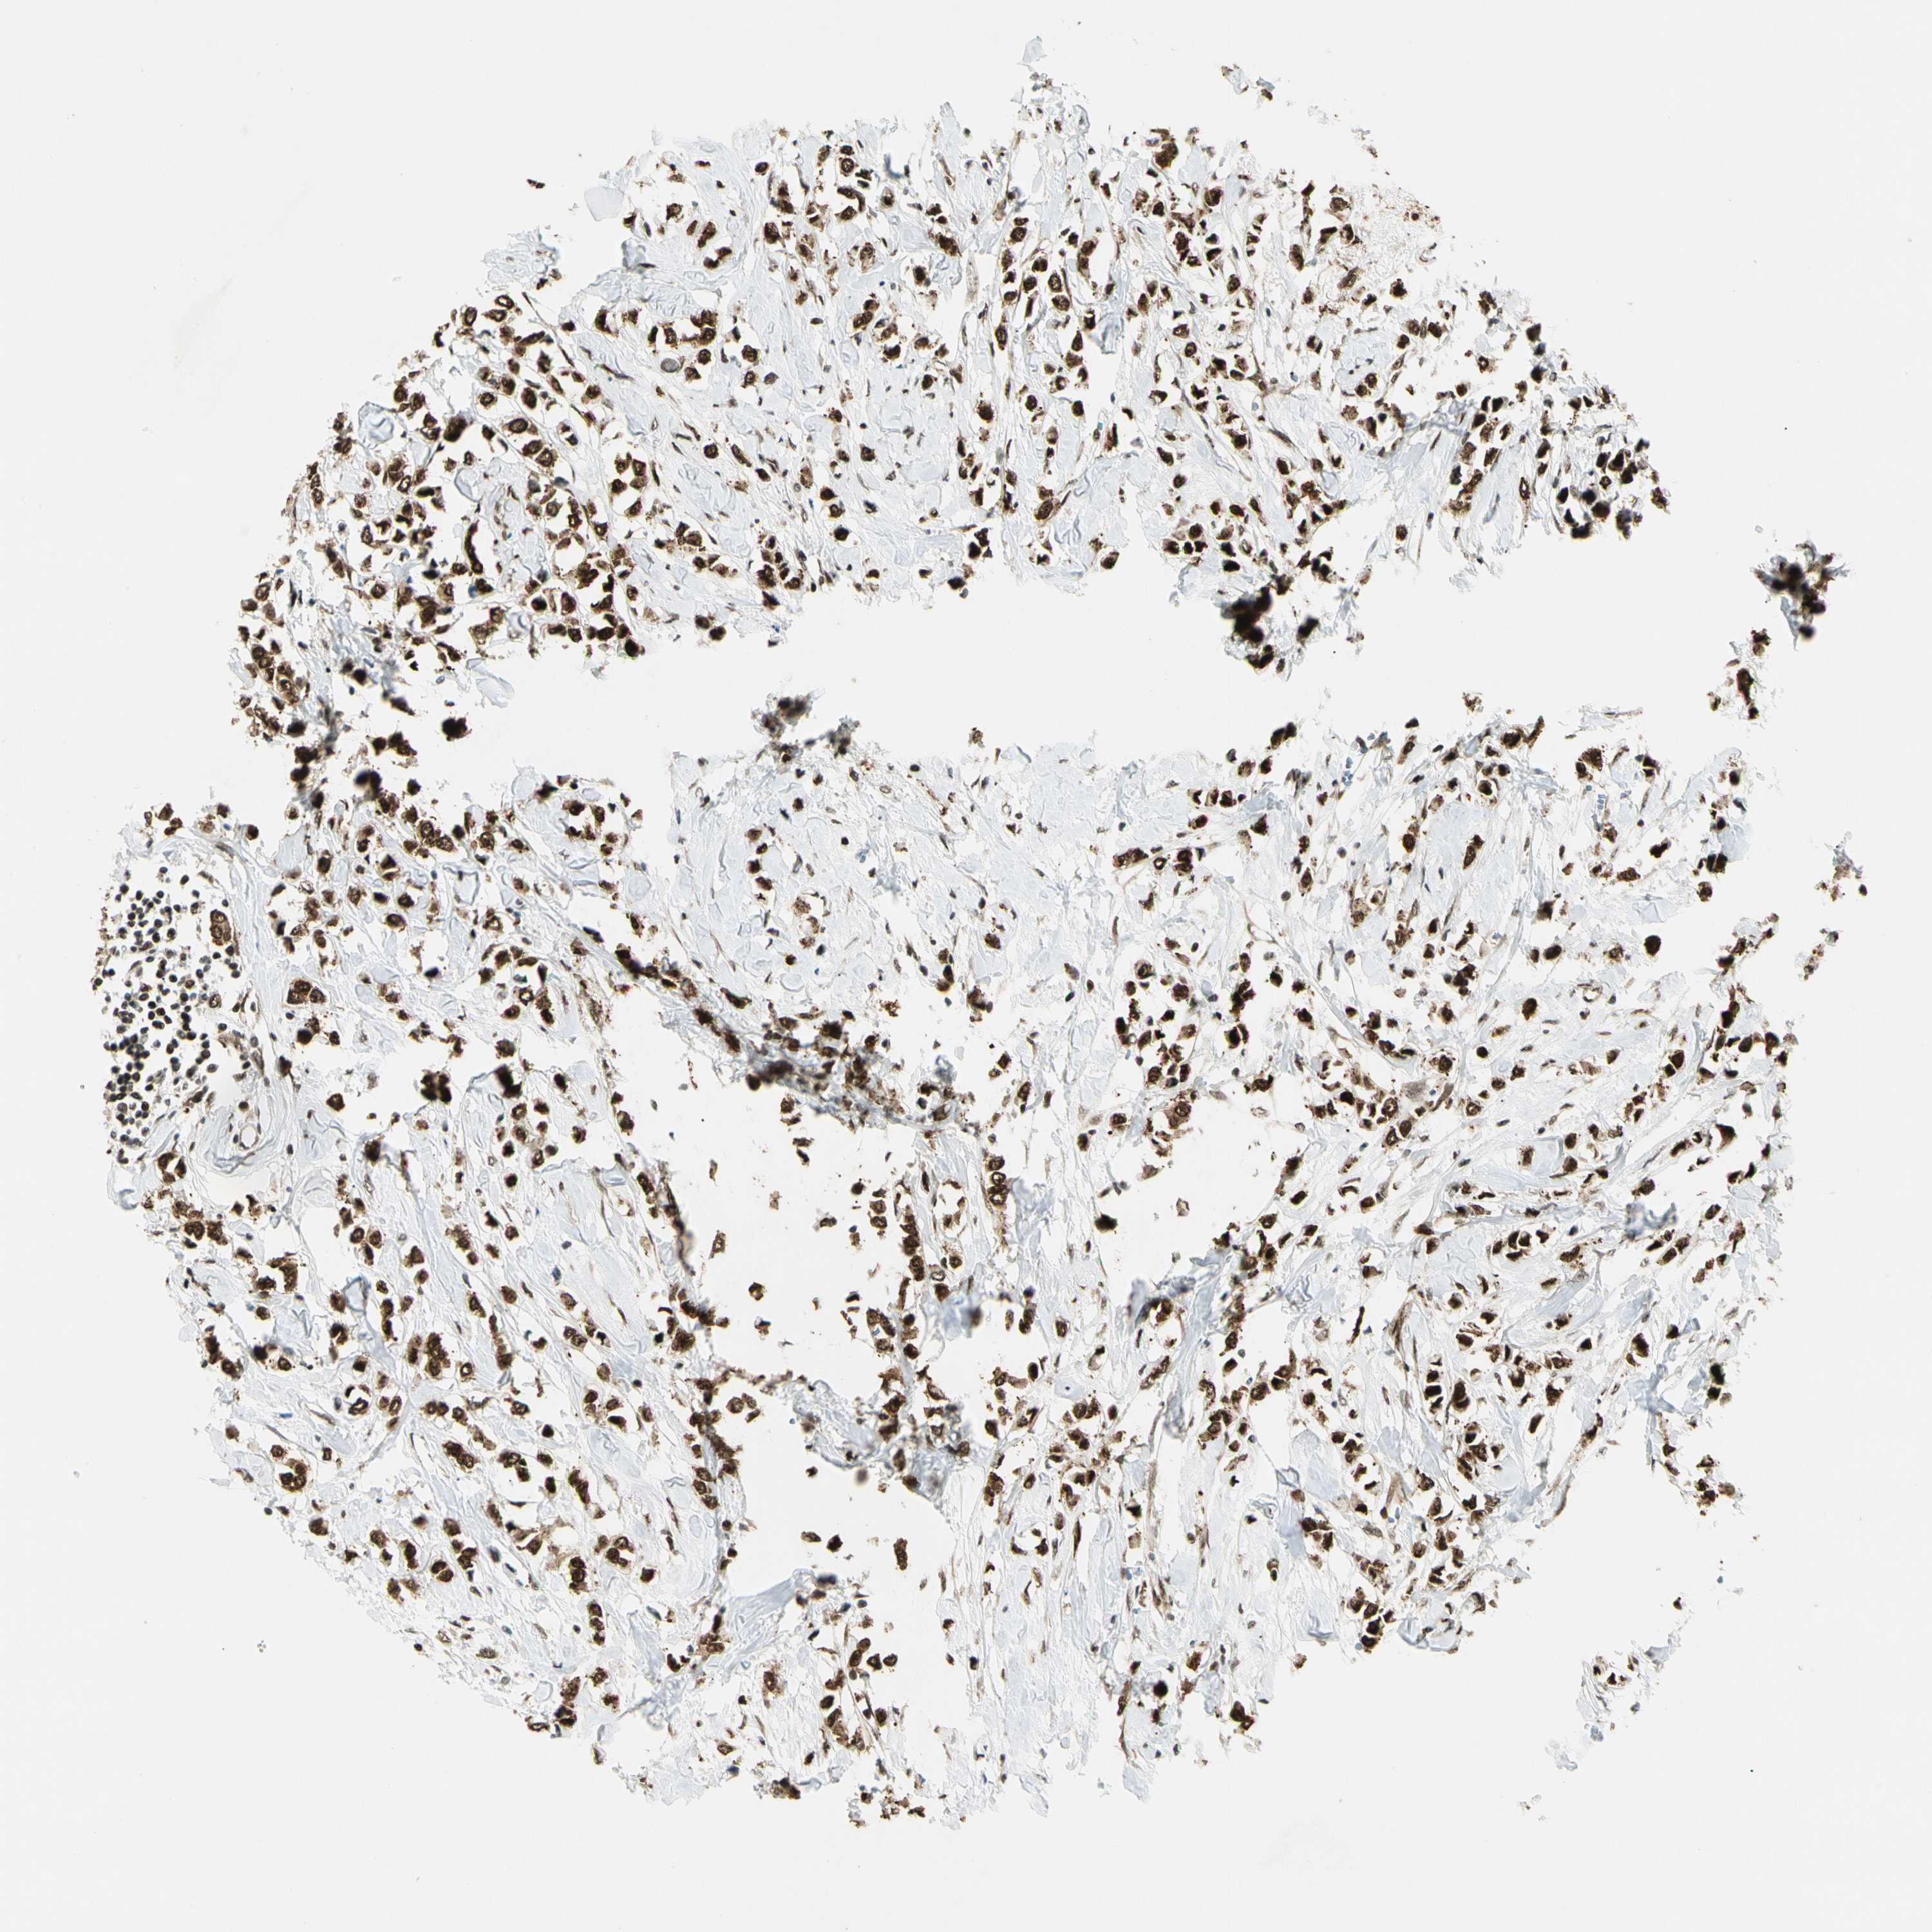

BRCA TCGA BRCA VALIDATION PROTEIN EXPRESSION